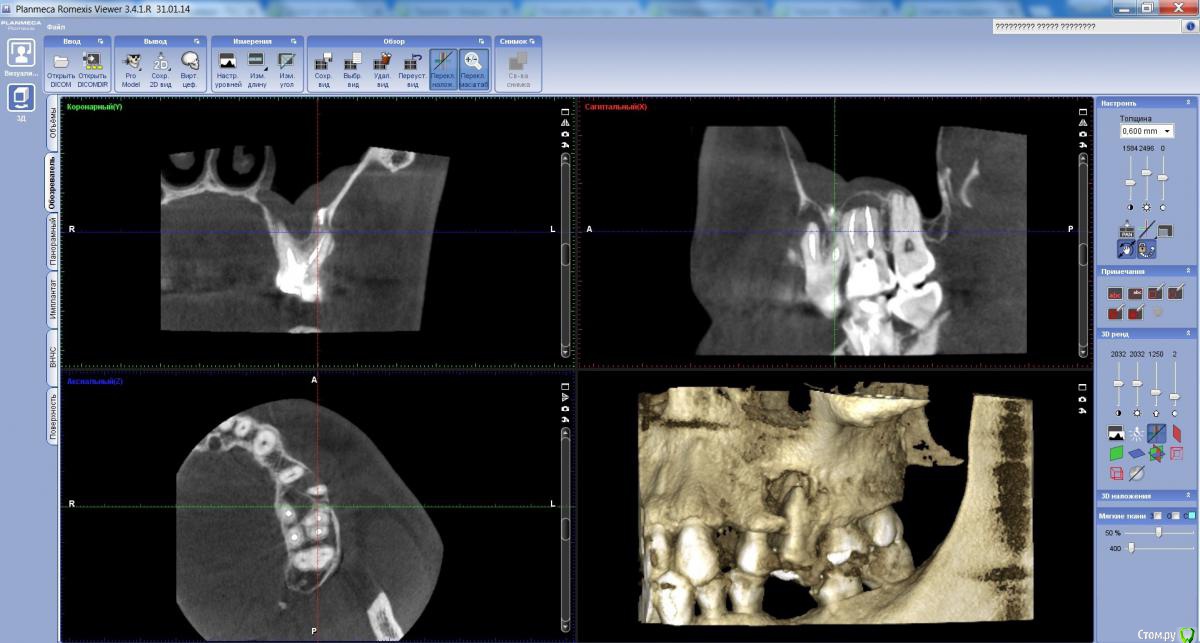

Но через 5 дней на повторном приёме парадонтолог посоветовал сделать томографию.

И по результату КТ - направили к хирургу на удаление 6 и 7 зубов...

Хирург говорит - удалять шестой.

Можно и нужно ли пытаться его вылечить без удаления?